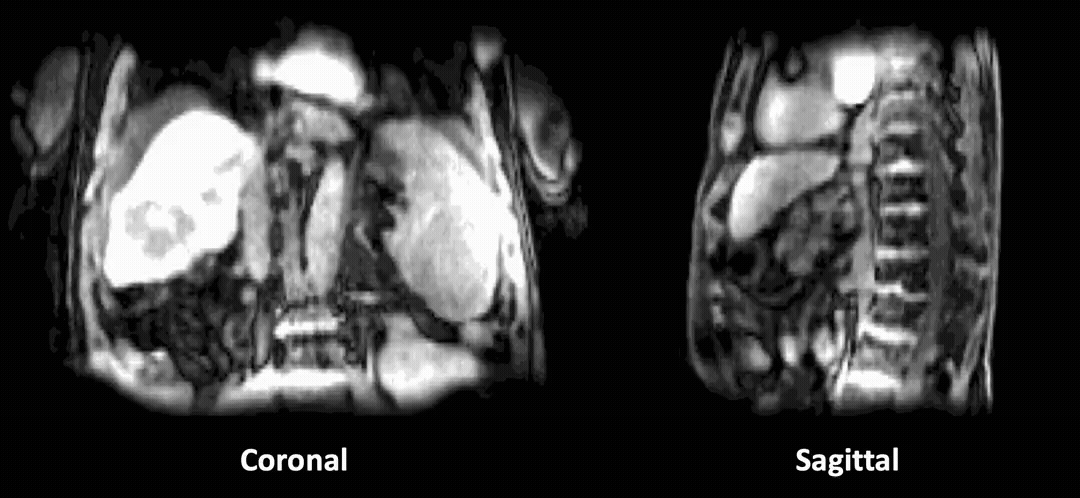

×Prospective Dynamic 3D MRI Reconstruction via Latent-Space Motion Tracking from Single MeasurementThe IEEE/CVF Conference on Computer Vision and Pattern Recognition